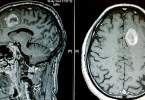

,消瘦不仅影响患者的外貌,更重要的是它可能标志着身体机能的下降和免疫力的减弱。长期的消瘦和营养不良还可能导致患者体力衰竭,增加感染和其他并发症的风险。在肿瘤治疗中,保持患者的营养状况和体重稳定是非常重要的,因为这有助于提高治疗耐受性和生存质量。在肿瘤治疗过程中,应密切关注患者的营养状况,并采取必要的措施来预防和减轻消瘦。如果有任何异常的消瘦症状建议及时就医。